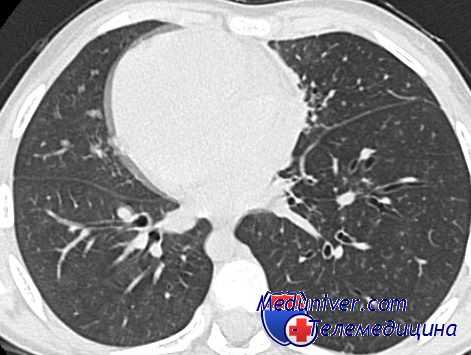

Для того, чтобы исключить влияние различных величин концентрации кислорода в инспираторной фракции при ИВЛ и ВЧС ИВЛ, во всех случаях вентиляция осуществлялась воздухом (FIO2 = 0,21). Результаты исследования представлены на рис. 3.

Рис. 3. Рис. 3.Респираторная механика и газообмен при традиционной двулёгочной

(ДИВЛ), традиционной однолёгочной (ОИВЛ), высокочастотной двулёгочной (ДВЧВ)

и высокочастотной однолёгочной (ОВЧВ) вентиляции.

Материалы, представленные на диаграммах и в таблице рис. 3, позволяют обсудить несколько феноменов, возникающих при ОВЧВ.

При ОВЧВ отмечается достоверно больший объём альвеолярной вентиляции (VA), чем при ОИВЛ и ДВЧВ. И если различия в VA между ОВЧВ и ОИВЛ легко объяснить существенной разницей в величинах минутной вентиляции (VЕ), то различия с ДВЧВ, на первый взгляд, представляются противоестественными, т.к. и дыхательный, и минутный объёмы вентиляции у них одинаковые. Однако если учесть, что при ОВЧВ эти объёмы распределяются в условиях вдвое уменьшенной ёмкости лёгких, то станет понятным, что их влияние на формирование объёма альвеолярной вентиляции возрастает как минимум вдвое. Этим, по-видимому, и можно объяснить данный феномен. Подтверждением правильности такого объяснения является факт одинакового удельного веса VA в составе VE как при ОВЧВ, так и при ДИВЛ, когда имеет место вдвое бόльший, чем при ОВЧВ, дыхательный объём.

В сравнении с ДИВЛ при ОВЧВ регистрируется достоверно меньший объём VAD и его удельный вес в составе альвеолярной вентиляции (VAD/VA), что объясняется более эффективным внутрилёгочным распределением дыхательных газов. Это подтверждается анализом величин статического комплайнса. При ОВЧВ он достоверно ниже, чем при ДИВЛ и ДВЧВ и составляет 19,8±4,7 мл∙см вод.ст (-1) против 34,9±4,7 и 20,7±6,5 мл∙см вод.ст(-1) соответственно (Р=0,000)*1 .Напомним, что снижение статического комплайнса при ВЧС ИВЛ, в отличие от традиционной вентиляции, указывает на большее число вентилируемых альвеол и более эффективную внутрилёгочную кинетику газов.

При ОВЧВ отмечается достоверно меньшее, чем при ДВЧВ напряжение кислорода в артериальной крови (РаО2), что следует рассматривать как результат более высокого веноартериального шунта (QS/QT). Коэффициент корреляции РаО2 и QS/QT при ОВЧВ составляет -0,97 (P=0,000).

При традиционной ИВЛ и ОВЧВ величины этих параметры не различаются (Р=0,091),т.е.наличие тотального ателектаза половины лёгочной паренхимы при ОВЧВ никак не отражается на величинах шунта и РаО2. Единственным объяснением этого явления может быть то, что при ОВЧВ в сравнении с ИВЛ на 82% меньше VAD и в 5 раз меньше его удельный вес в составе альвеолярной вентиляции.

Этот факт позволяет предположить, что высокая эффективность кинетики газов в вентилируемом легком при ОВЧВ компенсирует негативные влияния ателектаза оперируемого лёгкого. Поэтому величины шунта и артериального напряжения кислорода при традиционной ИВЛ и ОВЧВ не различаются.

Ещё одним доказательством этого являются результаты сравнения параметров респираторной механики и газообмена при обоих вариантах ВЧС ИВЛ, поскольку в силу одинаковых условий внутрилёгочного распределения дыхательного газа влияние ателектаза оперируемого лёгкого проявляется отчётливо. При ОВЧВ отмечается достоверное увеличение шунта и снижение РаО2, что объясняется различиями в величинах VAD и VAD/VA.

И хотя различия в величинах данных параметров при этих вариантах ВЧС ИВЛ существенно меньше в сравнении с традиционной ИВЛ, и составляют соответственно 18% и 43%, уменьшение VAD и VAD/VA при ОВЧВ, по-видимому, оказывается недостаточным, чтобы полностью компенсировать негативное влияние ателектаза, как это наблюдается в сравнении с традиционной вентиляцией.

Наиболее отчётливо влияние ателектаза оперируемого лёгкого проявляется при однолёгочной традиционной вентиляции. В отличие от двулёгочного её варианта, в условиях ОИВЛ при одинаковых величинах VA/VE и VAD/VA определяется увеличение дыхательного мёртвого пространства более чем на 50% (Р=0,000). Причём это происходит в основном за счёт увеличения альвеолярного мёртвого пространства, о чем свидетельствует достоверное возрастание QS/QT (Р=0,01) и снижение РаО2 (Р=0,046).

Сравнение параметров респираторной механики при однолёгочных вариантах традиционной и высокочастотной струйной вентиляции свидетельствует о существенных преимуществах ВЧС ИВЛ. При её проведении отмечается снижение объёма дыхательного мёртвого пространства более чем в 2,5 раза, в 5 раз уменьшение удельного его веса в составе объёма альвеолярной вентиляции, на 83,5% снижение внутрилёгочного шунтирования крови, что сопровождается возрастанием напряжения кислорода в артериальной крови на 16,7%.